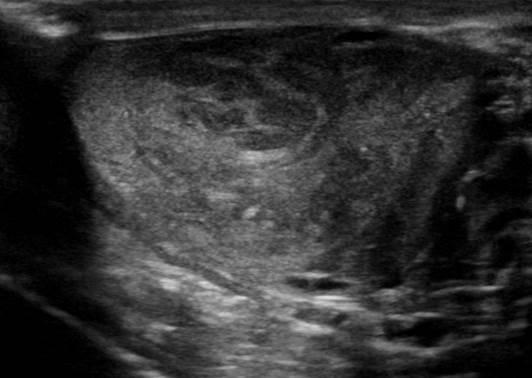

U tinh hoàn

» Thông tin: Nam giới – 35 tuổi.

» Lâm sàng: Sưng tinh hoàn.

# U tinh bào (Seminoma).